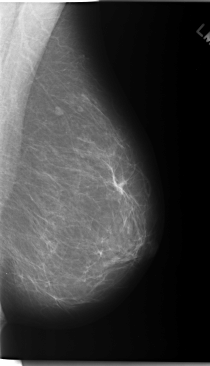

C_0169_1.LEFT_MLO

C_0169_1.LEFT_CC

LEFT_MLO LINES 5856 PIXELS_PER_LINE 3360 BITS_PER_PIXEL 12 RESOLUTION 50 NON_OVERLAY